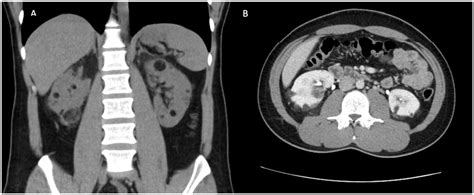

The diagnosis of an angiomyolipoma of the kidney relies heavily on medical imaging. Because these tumors contain macroscopic fat, they have a very distinct appearance on radiology scans. Radiologists use the following tools to identify them:

• Computed Tomography (CT) Scan: The gold standard for diagnosis. The presence of fat density within a kidney lesion is a hallmark of an angiomyolipoma.

The management approach is highly individualized. If the tumor is small and asymptomatic, the most common advice is "active surveillance." This means the patient returns for routine follow-up ultrasounds or scans every 6 to 12 months to ensure the tumor is not growing rapidly. However, if the tumor is large, symptomatic, or at high risk of rupturing, doctors may suggest one of the following interventions:

• Selective Arterial Embolization: A minimally invasive procedure where a radiologist blocks the blood vessels supplying the tumor, causing it to shrink.